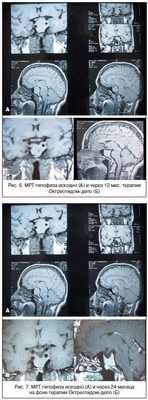

От предложенного нейрохирургического лечения отказалась, были назначены аналоги соматостатина длительного действия (Октреотид-депо, производитель «Фарм-Синтез», Россия), которые получала с августа 2005 по февраль 2006 г. в дозе 20 мг 1 раз в 28 дней. На фоне лечения: СТГ базальный - 24 мМЕ/л (-31% от исходного), ИРФ-1 - 453 нг/мл (101-267) (-47% от исходного) (рис.3,4); ТТГ, Т4 св. - без динамики. Также отмечалось клиническое улучшение в виде снижения частоты и интенсивности головных болей, уменьшения потливости и отечности лица. Выполнена МРТ головного мозга: эндо-, инфра-, супралатероселлярная макроаденома гипофиза 17*19*28 мм (суммарный объем - 4,33 см3, уменьшение на 44% от исходного объема).

У пациентки, несмотря на отсутствие полной «биохимической» ремиссии заболевания, отмечена выраженная положительная динамика размеров опухоли, сопровождавшаяся регрессией клинических симптомов (рис. 5, 6).